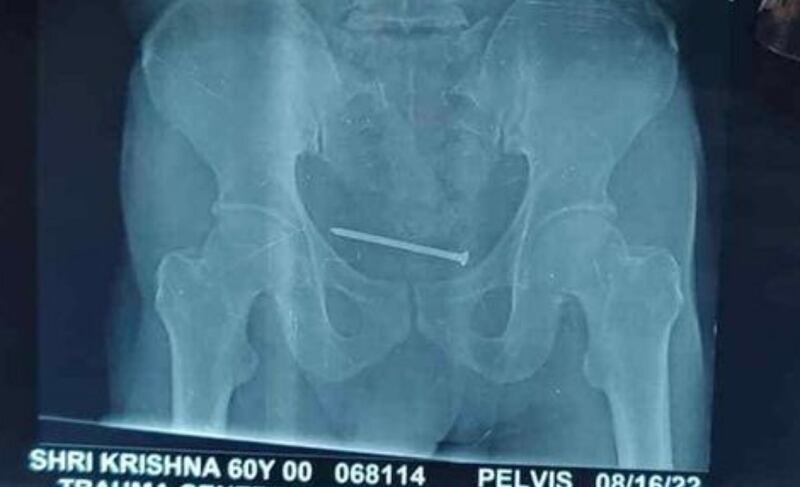

E embora os médicos pensassem que as dores de Jagram aconteciam possivelmente por problemas no coração, esta hipótese foi descartada depois que Prateek Mishra, doutor que acompanhou o paciente nesse período, resolveu solicitar um raio-x e exame ultrassom.

Embora os médicos não tivessem certeza de como foi parar em tal local, eles tinham uma confirmação: Jagram tinha um prego de cerca de 10 centímetros em sua bexiga, o que além de gerar muita dor, é algo que pode ser considerado “enorme” para tal zona do corpo humano.

Agora, o homem indiano está bem de saúde e já não apresenta as mesmas dores que o incomodavam antes. Uma foto mostrou o tamanho do prego retirado.